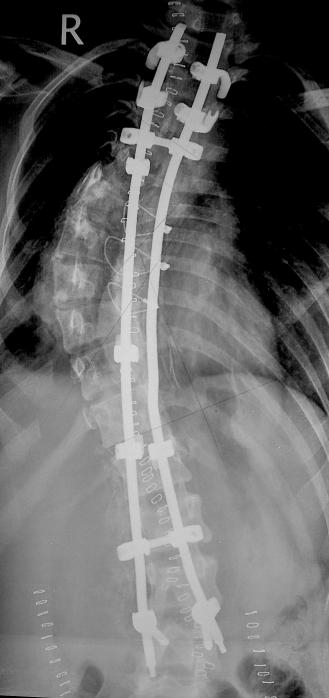

Post operative X-rays standing erect PA & Lateral, after 10 days of surgery. Clinical picture after a month. Segmental fixation with hooks, pedical screws & rods.

Post-op

Post op Xray